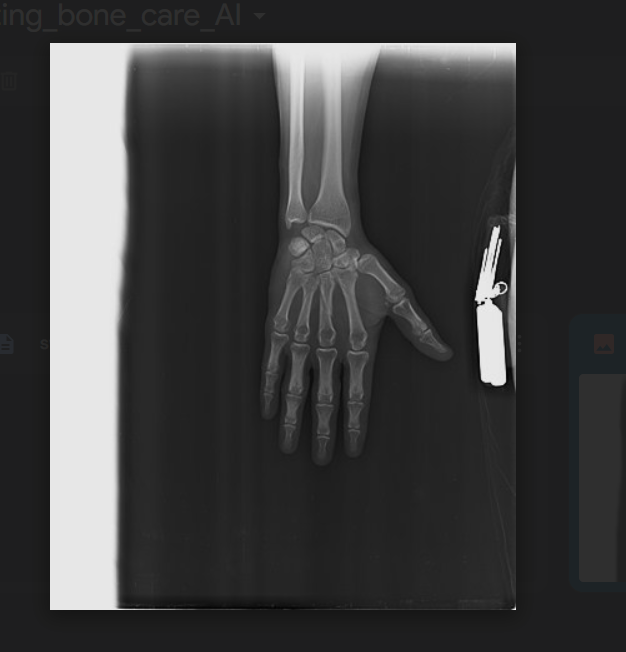

Bonecare AI is a complete platform for diagnosing and managing bone fractures. Using a deep learning model, the platform can analyse photos to detect whether a bone is broken and offer a full report of the results. This tool allows users to immediately spot fractures and respond appropriately based on the AI's advice.

In addition to fracture identification, Bonecare AI provides pain management summaries to assist reduce the suffering associated with fractures. The platform has information about various types of fractures, typical symptoms, and suggested treatments, making it an invaluable resource for both patients and healthcare providers. The user-friendly layout allows anybody to quickly explore the website and get the information they need.

We developed Bonecare AI employing a variety of modern technologies and frameworks. The deep learning model at the heart of our platform was built with TensorFlow and PyTorch, allowing us to design a strong neural network capable of properly recognising fractures from medical photos. We trained the model on a wide range of x-ray and MRI images to assure its accuracy and dependability.

We are proud to have created a deep learning model that can effectively detect bone fractures from medical photographs and also generate summaries to that images Up to 90.3% accuracy . Our model's high accuracy and dependability are major milestones that demonstrate AI's promise in enhancing medical diagnostics. This result demonstrates our team's devotion and experience in both artificial intelligence and medical imaging.